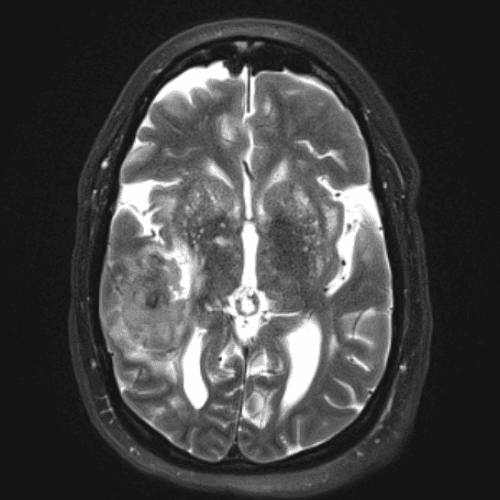

๋‹น์ง ์‹œ ํ”ํžˆ ๋ณผ ์ˆ˜ ์žˆ๋Š” ์‚ฌ๋ก€์˜ ์ „ํ˜•์ ์ธ ์˜ˆ๋ฅผ ํฌํ•จํ•ฉ๋‹ˆ๋‹ค.

39 ์‚ฌ๋ก€

์—ฐ์Šต

๋ฏธ๋ฌ˜ํ•˜๊ฑฐ๋‚˜ ์–ด๋ ค์šด ์‚ฌ๋ก€์™€ ์ผ๋ถ€ ์ •์ƒ ์‚ฌ๋ก€๋ฅผ ํฌํ•จํ•˜์—ฌ ๋‹น์ง์„ ์‹œ๋ฎฌ๋ ˆ์ด์…˜ํ•ฉ๋‹ˆ๋‹ค.

50 ์‚ฌ๋ก€